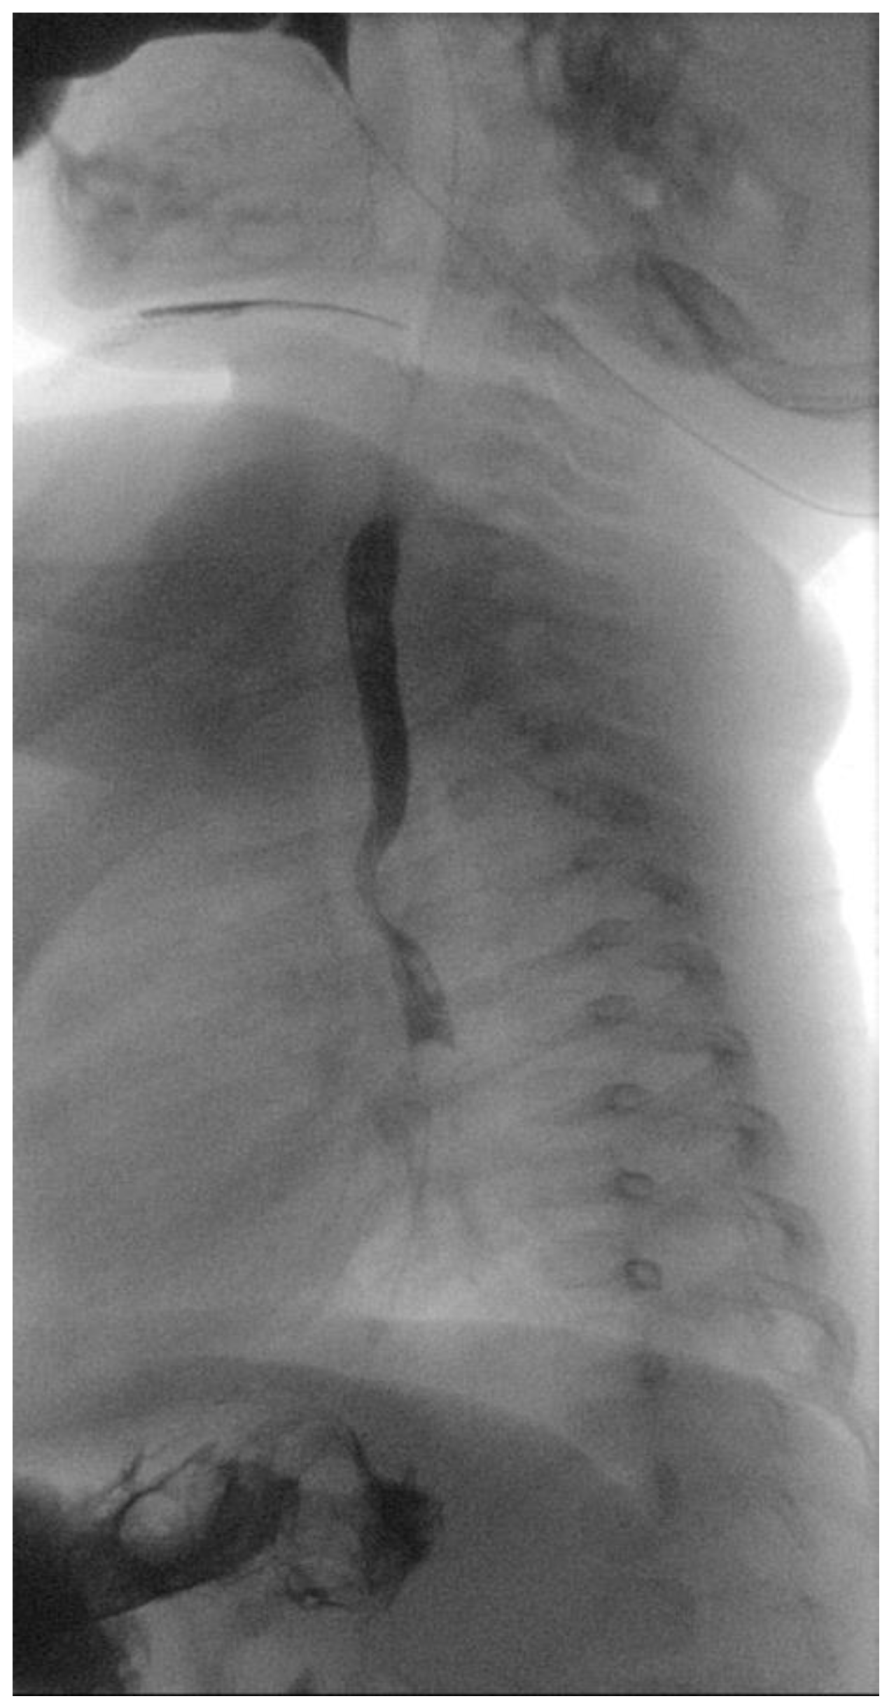

A 5-month-old female patient was being evaluated for failure to thrive secondary to dysphagia while on a liquid diet, requiring feeding aids (nasogastric tube). Past medical history accounts for in utero umbilical hemorrhage at 34 weeks’ gestation and intrauterine growth restriction. A barium swallow test was performed that revealed a posterior indentation of the proximal thoracic esophagus (Figure 1).

Figure 1. Barium swallowing test. Posterior indentation of the proximal thoracic esophagus.